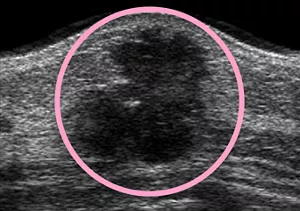

● 超音波診断装置(エコー)

人間の耳には聞こえない超音波を機械から発し返ってくる反射の様子を画像化。

手に触れない数ミリのしこりを見つけだすことができます。

検査時間は10分程度で、痛みなどはまったくなく、身体に無害です。

妊娠中、若年の方、頻繁に検査をする必要のある方などに適しています。